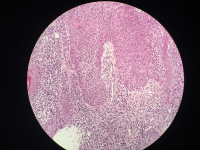

女性,鼻背部肿物3年,活检直径0.5厘米,

• 图2

考虑皮肤鲍温病

刺激性脂溢性角化病

高分化鳞癌

考虑鲍温氏病。

反转性毛囊角化病

激惹型脂溢性角化病。

日光性角化病